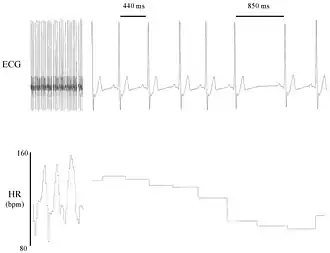

La variabilidad de la frecuencia cardíaca (VFC) es el fenómeno fisiológico de la variación en el intervalo de tiempo entre cada latido cardíaco. Se mide por la variación en el intervalo de latido a latido.

Otros términos utilizados incluyen: "variabilidad de la duración del ciclo", "variabilidad de RR" (donde R es un punto que corresponde al pico del complejo QRS de la onda de ECG ; y RR es el intervalo entre Rs sucesivas), y "variabilidad del período del corazón" .